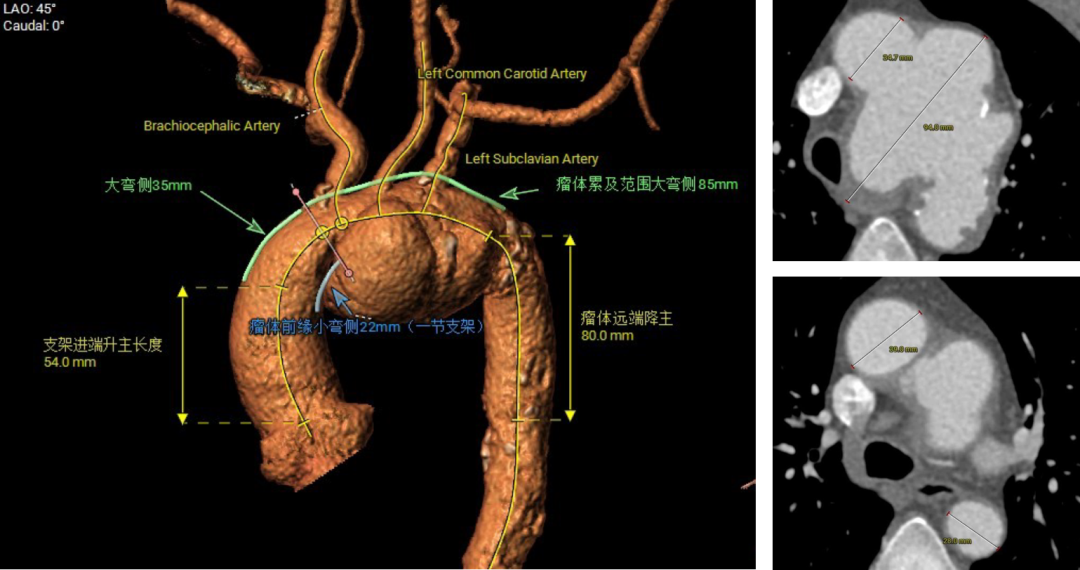

王X,男,57岁,主动脉弓动脉瘤。LSA、LCCA双内分支, IA开窗。

术前